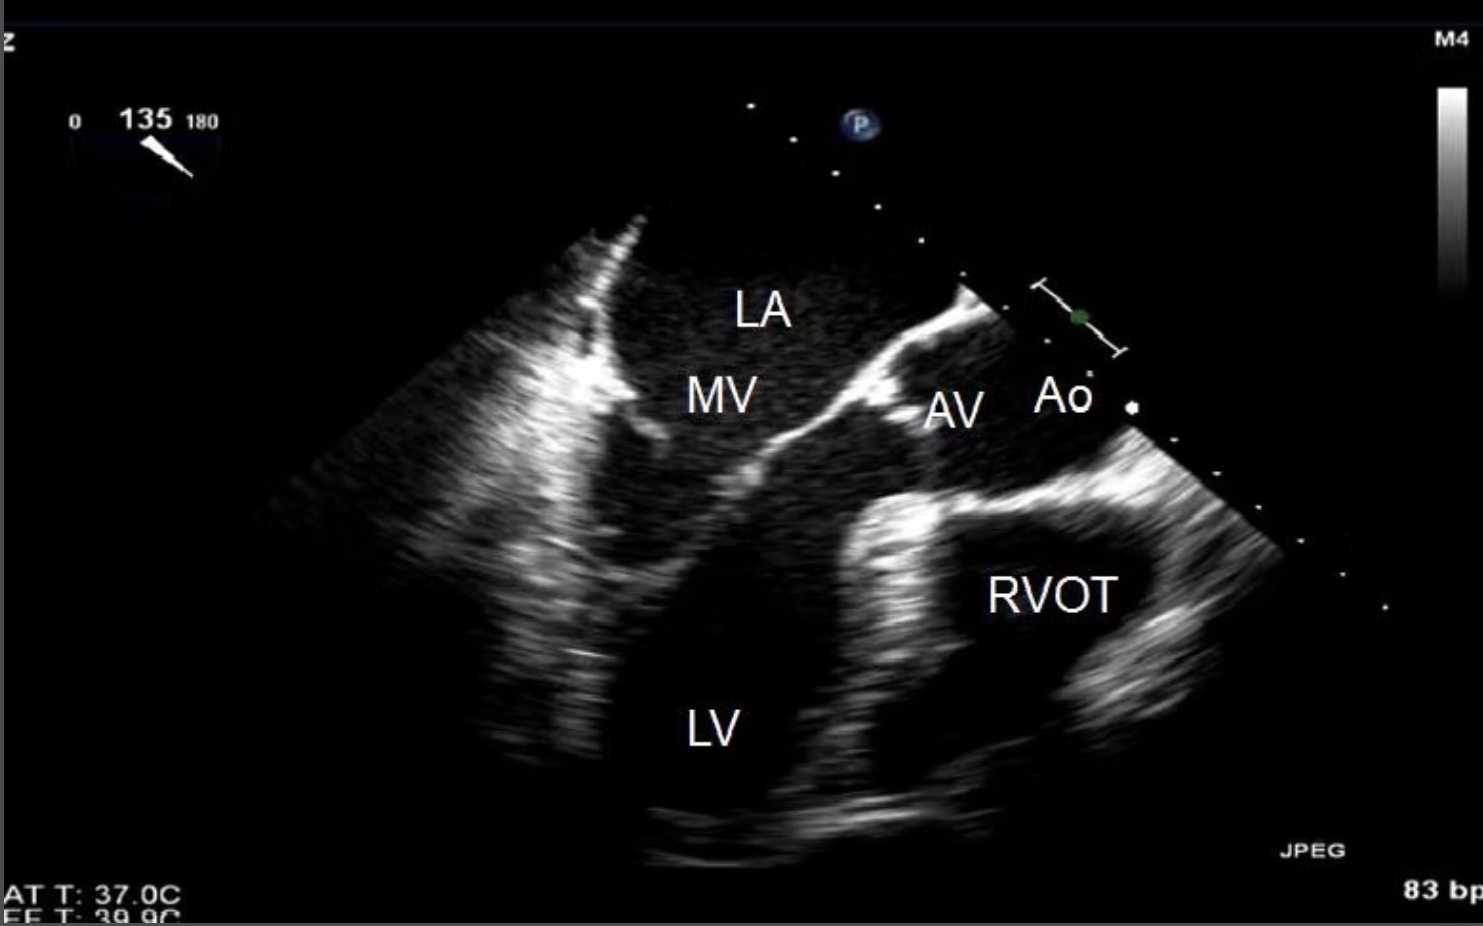

What view is this?

ME LAX

What transducer angle is used to obtain ME LAX?

120-140*

Which MV leaflets can be evaluated on the ME LAX view?

A2-P2